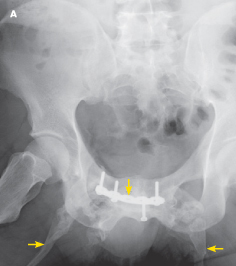

Myositis Ossificans

10/12/2012

Shailja Patel, MD; Satyajeet Roy, MD, FACP

<p class="p1"><img src="/sites/default/files/images/Screen%20shot%202012-10-12%20at%201.51.31%20PM.png" alt="sartorius musculature" title="sartorius...